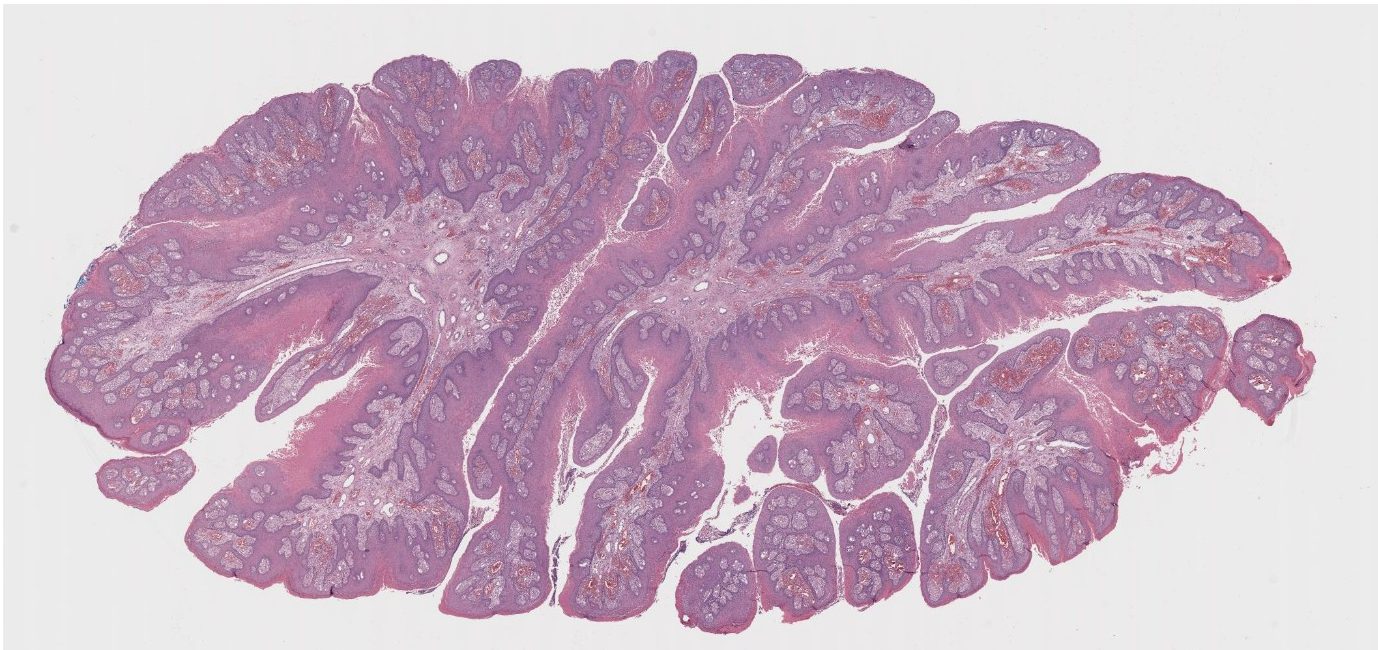

(Low-power histologic view of verrucous lesion)

On examination, several defining features stand out: